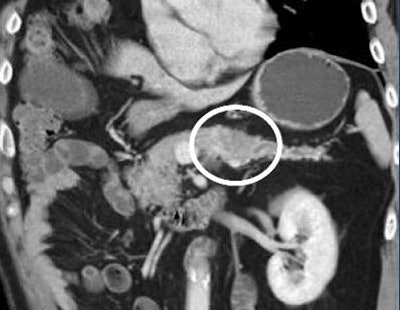

Perhaps a lesion is visible but not appreciated because it's more of a textural change than a discrete mass, Fishman said. Maybe there is only a dilated pancreatic duct or common bile duct without a discrete mass. But a dilated duct without an apparent mass should never be ignored, he said.

"If you see a dilated duct, there has to be a lesion present," Fishman said. If you don't see it, maybe do another study."

![]() |

| Patient has dilated pancreatic duct, but no tumor is visible. All images courtesy of Elliot Fishman, MD. |